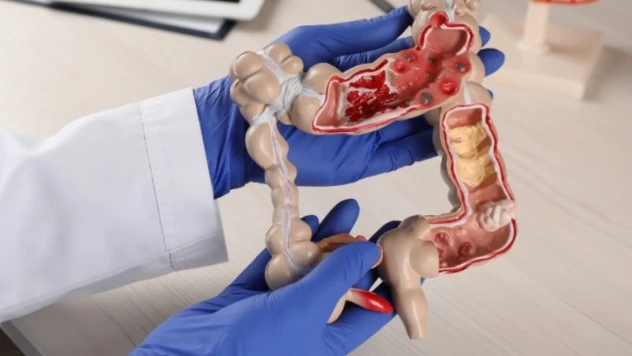

Devlet Hastanesi'nde Çocukluk Çağı Kanserine dikkat çekildi

Hastanede kansere dikkat çektiler

Sağlık Müdürlüğü’nden Kanser Tarama Programına davet

Sağlık Müdürlüğü Rahim Ağzı Kanserine dikkat çekti